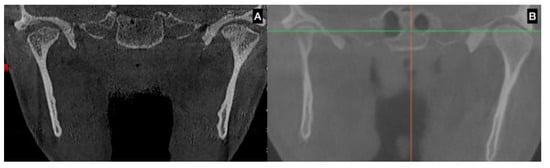

| CBCT | Augmentation in condylar size in comparison to the non-hyperplastic condyle |

| Lack in upper cortical line of the affected condyle in the upper area showing an active metabolism | |

| Augmentation in radiolucency in the affected condyle with an image related to poor density in some cases | |

| SPECT | Differences 10% in caption of the radioisotope between the hyperplastic and the non-hyperplastic condyle |